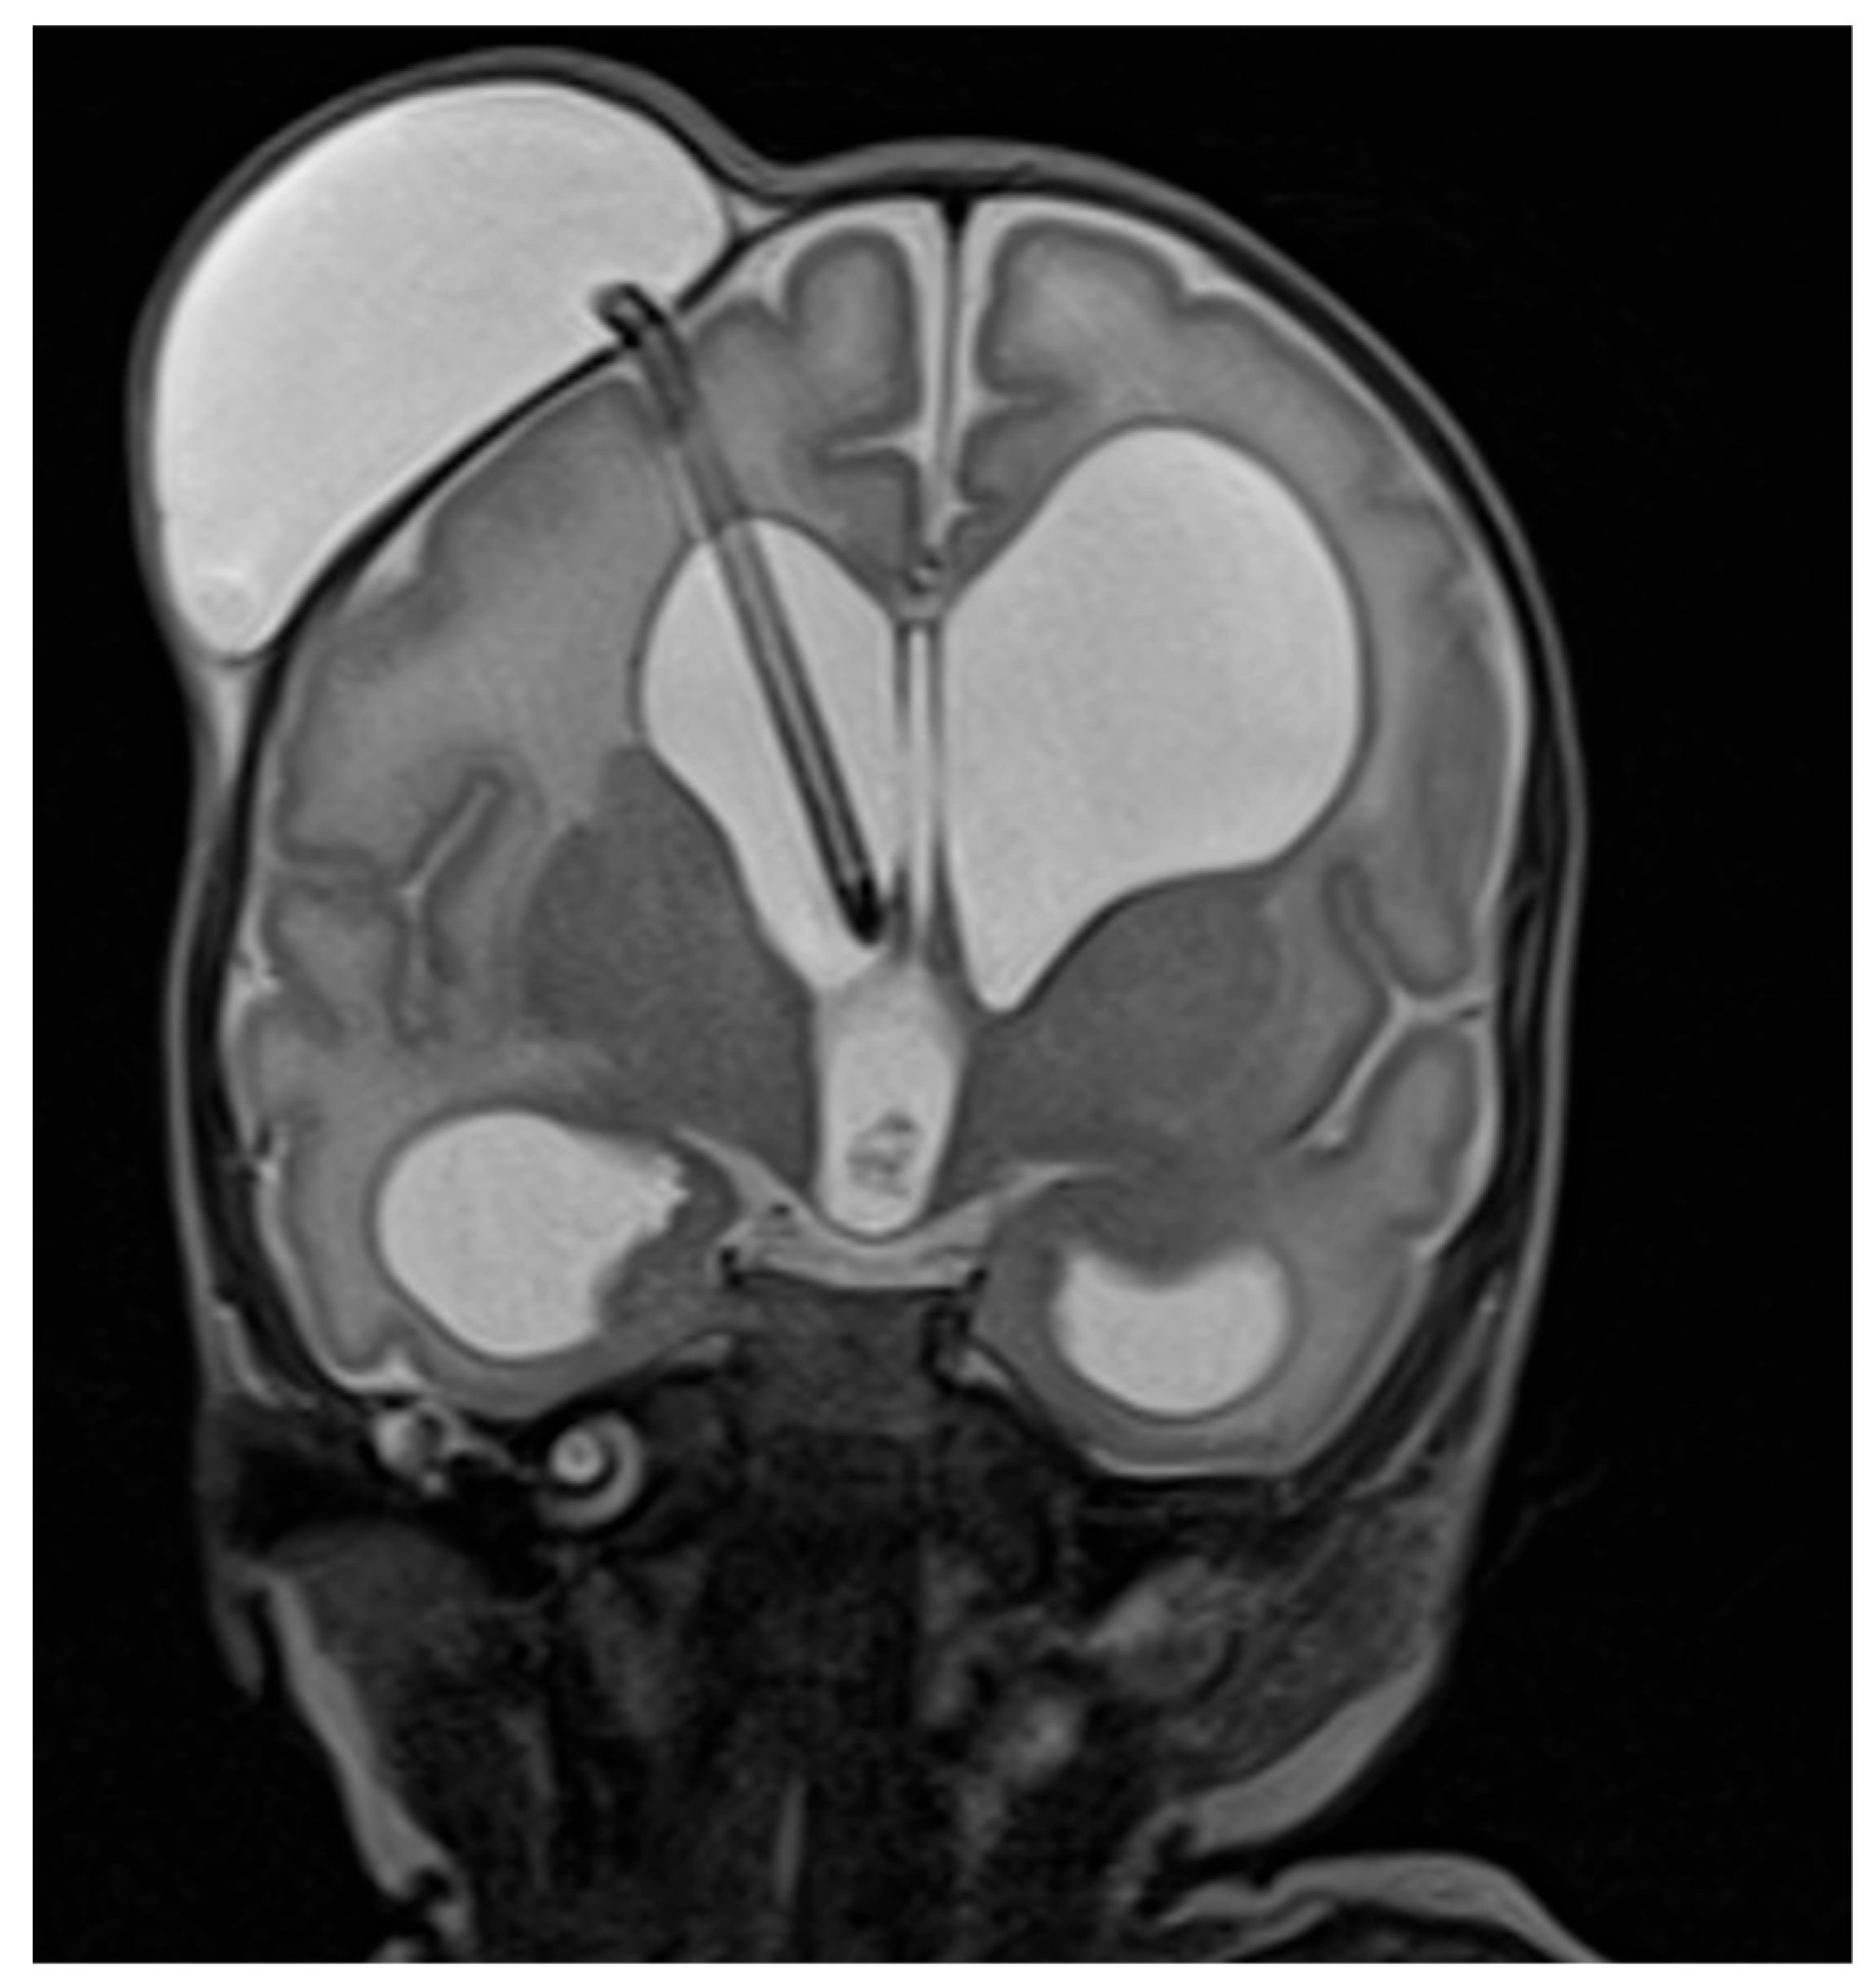

3.4. Treatment

| Shunt side, n (%) Right Left | 23 (72%) 9 (28%) |